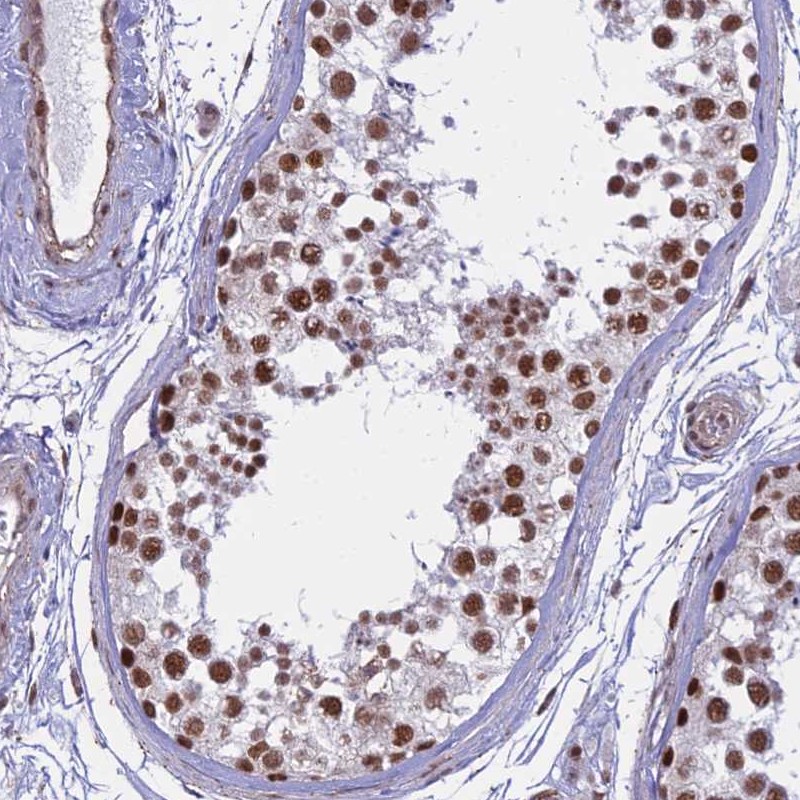

Immunohistochemical staining of human testis shows strong nuclear positivity in cells in seminiferus ducts.